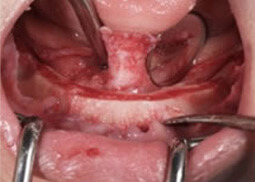

多くのケースにおいて、戦略的な顎骨のボーンリダクション(骨削除)が必要となります。計算されたボーンリダクションを行う事で、長期に渡る審美性と清掃性を得る事が可能となります。計算された顎骨のボーンリダクションを行うことで、顎骨を計算された形状に整形すると共に、歯肉の形態を理想的な形態に創りあげていきます。それにより、歯肉とストラクチャー(構造物)の基底部との間に汚れが付着する事を最小限に抑えます。汚れが詰りにくい環境をしっかりと作り上げていく。患者様にとって、これは非常に重要な事です。

ボーンリダクション前

ボーンリダクション後